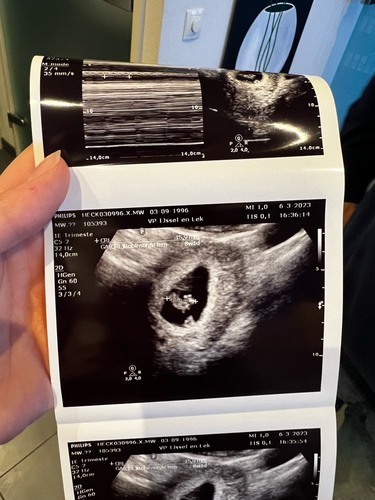

Dit is de ...

Ik weet niet hoe ik het moet zien. Zijn de cijfers die je ziet op de echo de onderkant of bovenkant ?

Dat was de bovenkant

Omdat het aan de rechterkant staat denk ik een jongen.